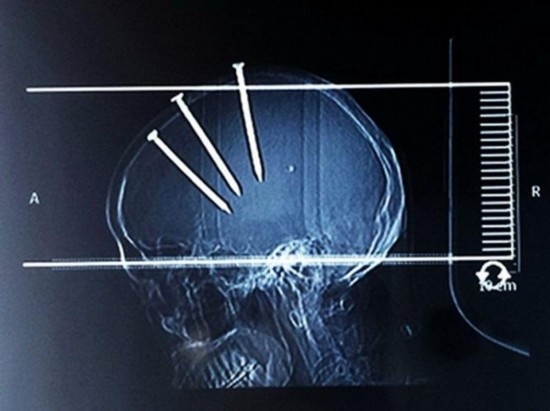

7591119148762357779.jpg

醫生們從一位69歲的男子頭部取下了三顆長釘。